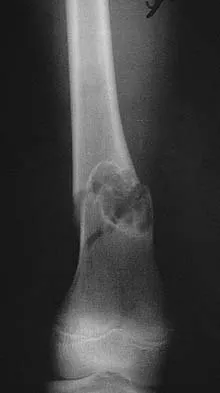

A 28-year-old man sustained numerous injuries in an accident including a dislocation of the elbow and a severe closed head injury that resulted in unconsciousness. The elbow was reduced in the emergency department. After 1 month of rehabilitation, the patient reports pain and stiffness. A radiograph is shown in Figure 23. Management should now consist of